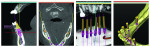

A cone-beam computed tomography (CBCT) scan was conducted and reformatted by 3D Diagnostics (www.3ddx.com) so that the implants’ placement could be planned with SimPlant® (Materialise Dental, www.materialisedental.com). The treatment modality selected was constructed so that the treatment would begin with three maxillary implants with a fixed bridge for the upper left quadrant and two implants in the No. 20 and No. 21 sites, which would be joined to future mandibular implants to fabricate a hybrid prosthesis or mandibular fixed implant bridge. The proper consent was received and the implants were placed during the first surgery.

The reformatting done by 3DDX allowed virtual placement of the implants and measurements from the existing teeth and roots to be used for pilot osteotomy placement. The loss of tooth No. 10 after initial treatment planning led to a decision to place implant No. 11 at a mesial angle so that the antero-posterior distance of the bridge could be optimized.

The implant planning for the initial implant placement was viewed in the SimPlant planner (Figure 6 though Figure 10) and MIS’s SEVEN® implants (www.mis-implants.com) were chosen for placement due to their cost effectiveness; sand-blasted and acid-etched surface, which increased the surface area; sterile single final drill; and implant stability at placement. The placement of five additional implants post-edentulation and mandibular ridge leveling can be seen in the SimPlant full window view. The SimPlant treatment plan was designed to address the edge to edge anterior bite. This would be done by performing an osteoplasty of the mandibular anterior and placing the implants in a more uprighted position with respect to the existing mandibular dentition. Placement of implants inferiorly and lingually would allow for a modification from a splayed Class III to a Class I occlusal relationship. The removal of the anterior teeth combined with osteoplasty and implant placement in a more inferior position would allow for maintaining her existing vertical dimension of occlusion. The patient agreed to the cost and number of implants, but she was given the option to leave the remaining lower teeth and place smaller-diameter implants in the posterior regions, so a treatment variation was created for this scenario as well. She wasn’t certain whether she could approve full mandibular edentulation until she evaluated the initial procedure’s success. Lastly, the maxillary full-arch treatment was planned to facilitate phase 2 treatment and provide her with an upgrade path.7